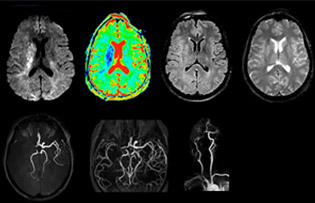

„In Frankreich werden Schlaganfälle in der Regel per MRT und nicht per CT untersucht, auch bei der Notfallbehandlung.“ „In Frankreich erfolgt die Bildgebung bei Schlaganfällen in der Regel per MRT, nicht per CT, auch bei der Notfallbehandlung. Das liegt daran, dass wir mit der MRT eine Ischämie in der akuten Phase direkt darstellen, aber auch Differenzialdiagnosen wie MS und Hämatom ausschließen können. Außerdem ist es uns möglich, die intrakraniellen und extrakraniellen Gefäße im Laufe derselben Untersuchung zu beurteilen“, sagt Dr. Savatovsky.

Die erste Herausforderung bei der Magnetresonanztomographie betrifft die Geschwindigkeit. Die Patienten werden in der Regel aus einem Rettungswagen in den MRT-Vorbereitungsraum gebracht und die Einrichtung erfolgt an einem separaten Platz außerhalb des Technikraums. „Der venöse Zugang wird während der neurologischen Untersuchung gelegt. Wenn es der zeitliche Abstand von den ersten Symptomen erlaubt, dass der Patient eine Thrombolyse erhält, führen wir eine sehr schnelle Untersuchung durch, die üblicherweise etwa 11 Minuten dauert, einschließlich der Pre-Scans. Bei einem transienten ischämischen Schlaganfall erfolgt im Regelfall zusätzlich eine ASL-Perfusionsbildgebung, weil bei manchen Symptomen mit negativer Diffusion ASL eine vaskuläre Ursache anzeigt.“

„Ingenia bietet eine große Flexibilität bei der Parametereinstellung, d.h., wir können eine Sequenz beliebig abstimmen“, erklärt Dr. Savatovsky. „Bei einer Schlaganfalluntersuchung nutzen wir zum Beispiel eine FLAIR-Sequenz von etwa zwei Minuten anstelle der vierminütigen Sequenz, die wir bei MS verwenden. Die Diffusionsbildgebung dauert 30 Sekunden, der T2*-gewichtete Scan ebenfalls 30 Sekunden und die Scan-Dauer bei der Angiographie beträgt weniger als eine Minute. Ingenia ist in dieser Situation ein großartiger Scanner. Auch bei diesen schnellen Sequenzen erzielen wir hochwertige Bilder mit einem guten Signal-Rausch-Verhältnis. Wenn wir anhand der ersten Sequenz feststellen, dass es sich nicht um einen ischämischen Schlaganfall, sondern um einen hämorrhagischen Schlaganfall handelt, können wir zu einer zeitaufgelösten Angiographie wechseln, um nach vaskulären Malformationen und einer Venenthrombose zu suchen.“

„Jede Klinik arbeitet anders, aber für mich umfasst das ideale Schlaganfallprotokoll die diffusionsgewichtete Bildgebung, die FLAIR- und die schnelle suszeptibilitätsgewichtete Bildgebung“, sagt Dr. Savatovsky. „Unsere schnelle suszeptibilitätsgewichtete Bildgebung dauert nur 50 Sekunden, sie ist also genauso schnell wie die T2*-gewichtete Bildgebung. Damit werden Blutungen, aber auch Koagulationen dargestellt. Wir führen zusätzlich eine 3D-MR-Angiographie durch, die Informationen über zervikale und zerebrale Gefäße liefert. Wenn die Patienten keine sofortige Behandlung benötigen oder wenn zusätzliche Informationen erforderlich sind, um über die Therapie zu entscheiden, nehmen wir außerdem eine Perfusionsbildgebung und eine T1-gewichtete Postkontrastbildgebung vor.“